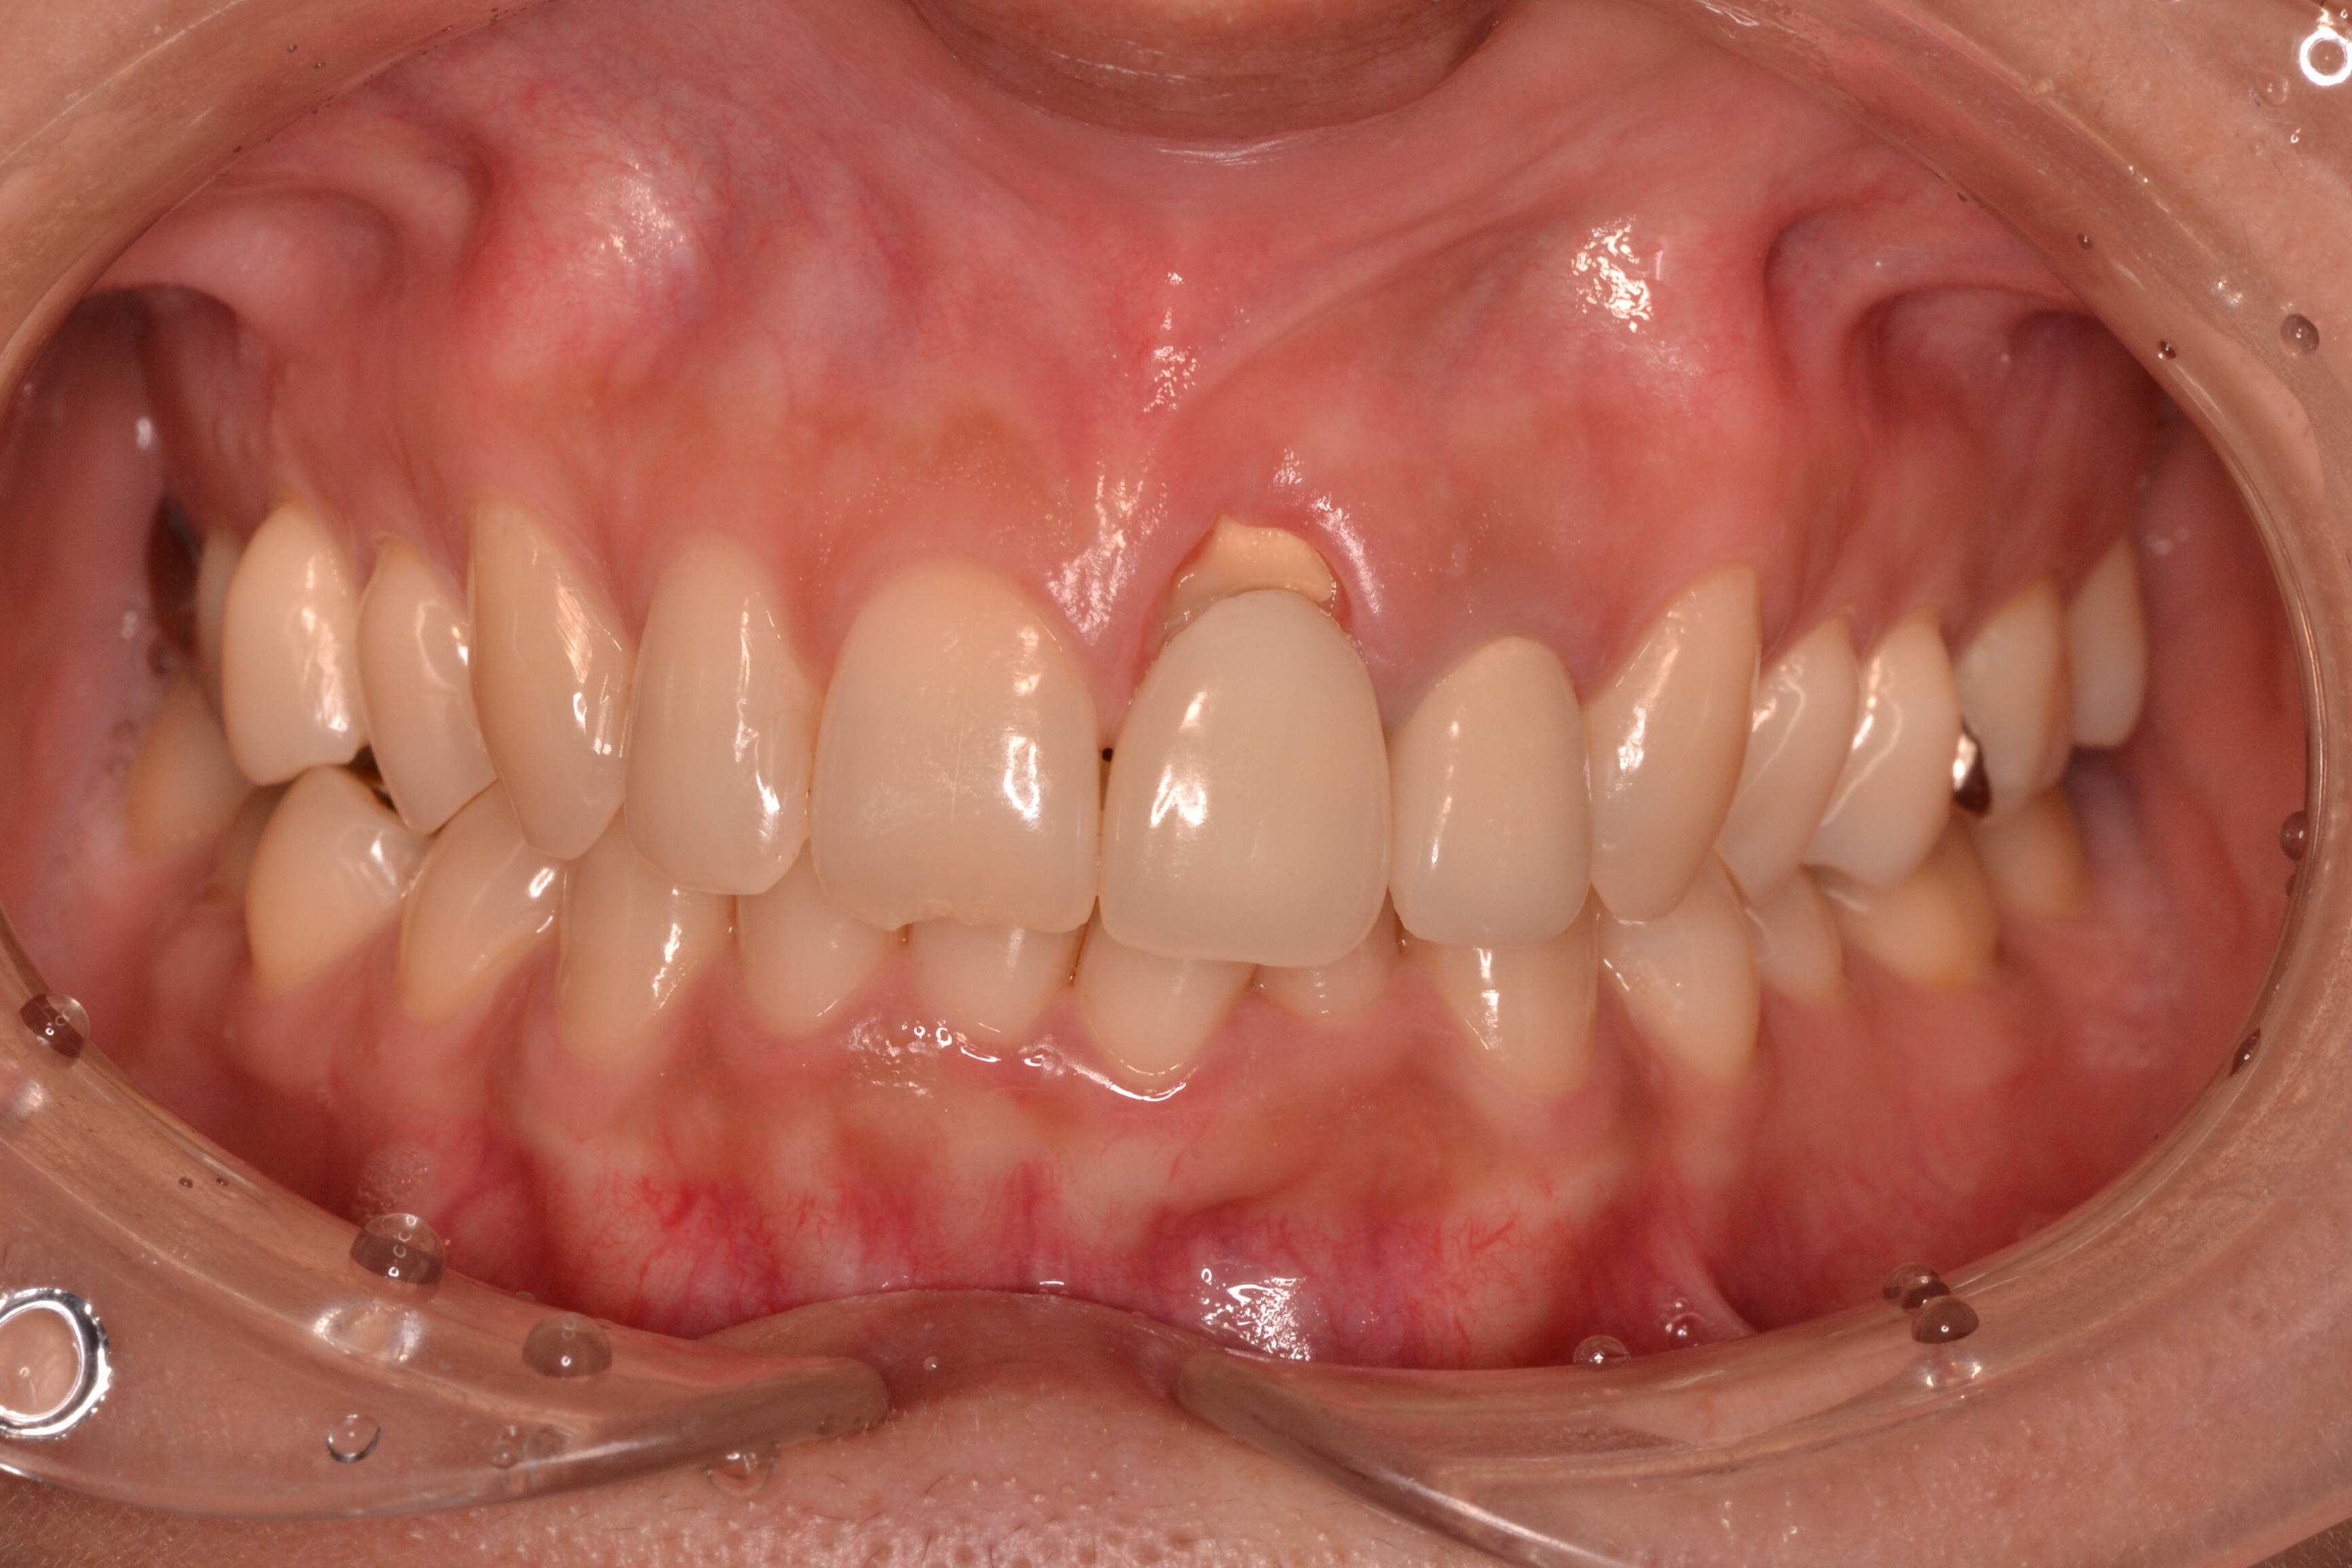

<治療前>歯根破折のため歯肉縁が下がってしまっています